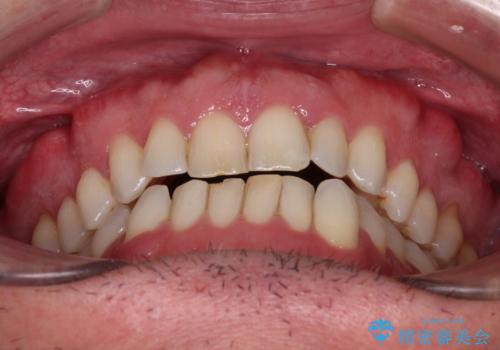

- 前歯でものを噛みきりたいとのことで来院された患者様です。

以前矯正治療を経験されたそうですが、舌の突出癖により上下前歯に隙間ができている様子でした。

前歯の非接触改善は、インビザラインの得意とするところですが、マウスピース矯正は絶対に継続できないとのことで、ワイヤー装置にて矯正治療を行うこととしました。